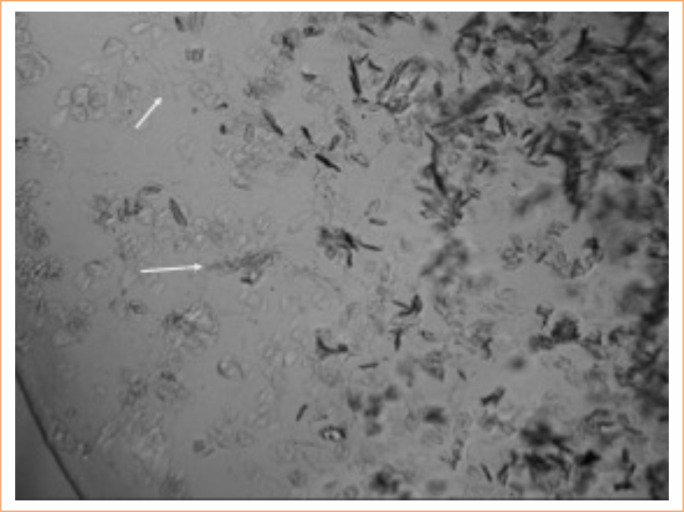

Methods: Time-mated pregnant Wistar rats were randomly divided into control and experimental groups. On gestational day 10, the experimental group received 10% ETU (130 mg/kg) by gavage, whereas the control rats received vehicle only. The embryos were harvested by cesarean section on gestational day 21. The fetuses exposed to ETU were divided into two groups: affected (without any clear anorectal alterations); and the malformed (with anorectal anomaly). The neuromotor plates were identified by immunohistochemistry with acetylcholinesterase, and alterations in the sacral region were evaluated by histological and morphometric studies.

Results: We used 43 control fetuses, 82 affected fetuses, and 118 malformed fetuses in this study. The most frequent associated macroscopic anomalies were spina bifida (55 fetuses), encephalocele (20), and alterations in the lower limbs (5). The sacroiliac was malformed in 45% of the affected fetuses and in 53.2 % of the malformed fetuses.

Conclusion: ETU leads to a reduced number of motor neurons in the pelvic musculature of both the malformed and the affected rats. The enteric neurons are altered in the malformed fetuses, but not in the affected ones. Both the affected and malformed rats exhibit sacral alterations that do not interfere with neurons.